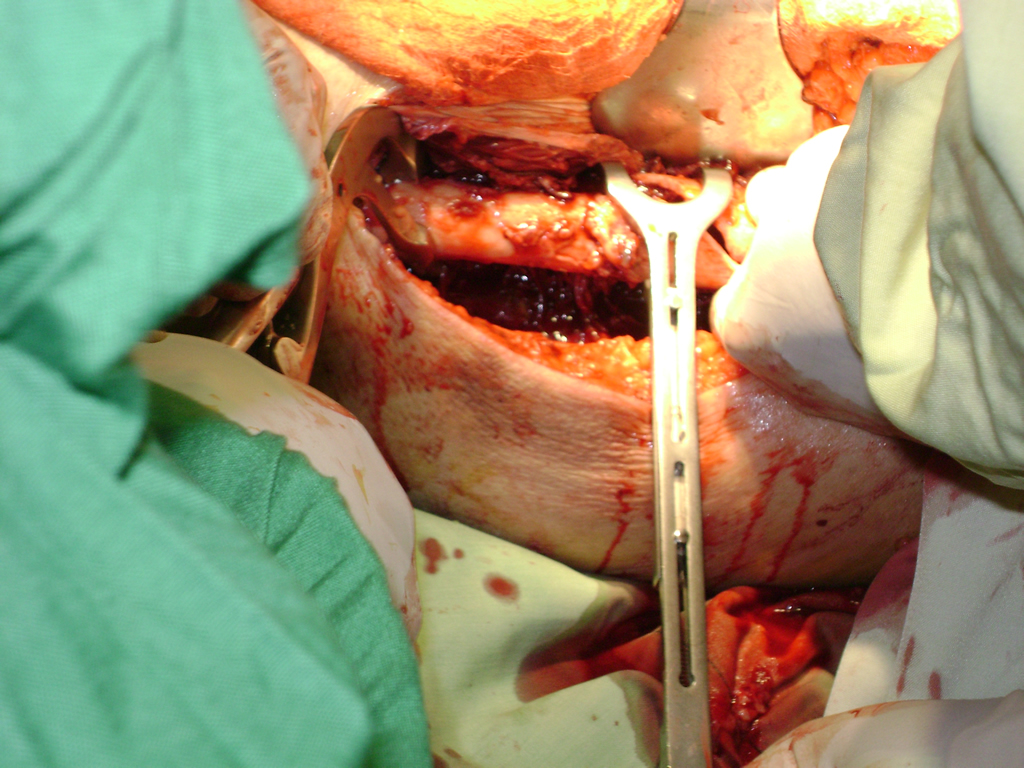

A menudo se recomienda la cirugía para reparar la fractura debido a dichos riesgos.

De esta forma nos ponemos a tus órdenes, somos conocedores de estos tipos de problemas, visitarnos será un gusto el poderte ayudar. cualquier inquietud puedes escribirnos al correo Esta dirección de correo electrónico está siendo protegida contra los robots de spam. Necesita tener JavaScript habilitado para poder verlo.